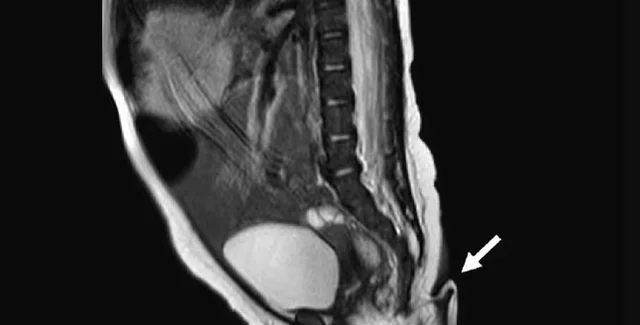

Відросток видалили під місцевою анестезією

Після цього хірурги провели невелику операцію під місцевою анестезією, щоб видалити відросток. Операція пройшла успішно і дитину виписали з лікарні того ж дня.

Дослідники продовжили вивчати "хвіст". Аналіз показав, що він складається з м'яких тканин, артерій, вен та пучків нервів. Загалом у світі зареєстровано лише 195 випадків людських "справжніх хвостів" (до 2017 року).